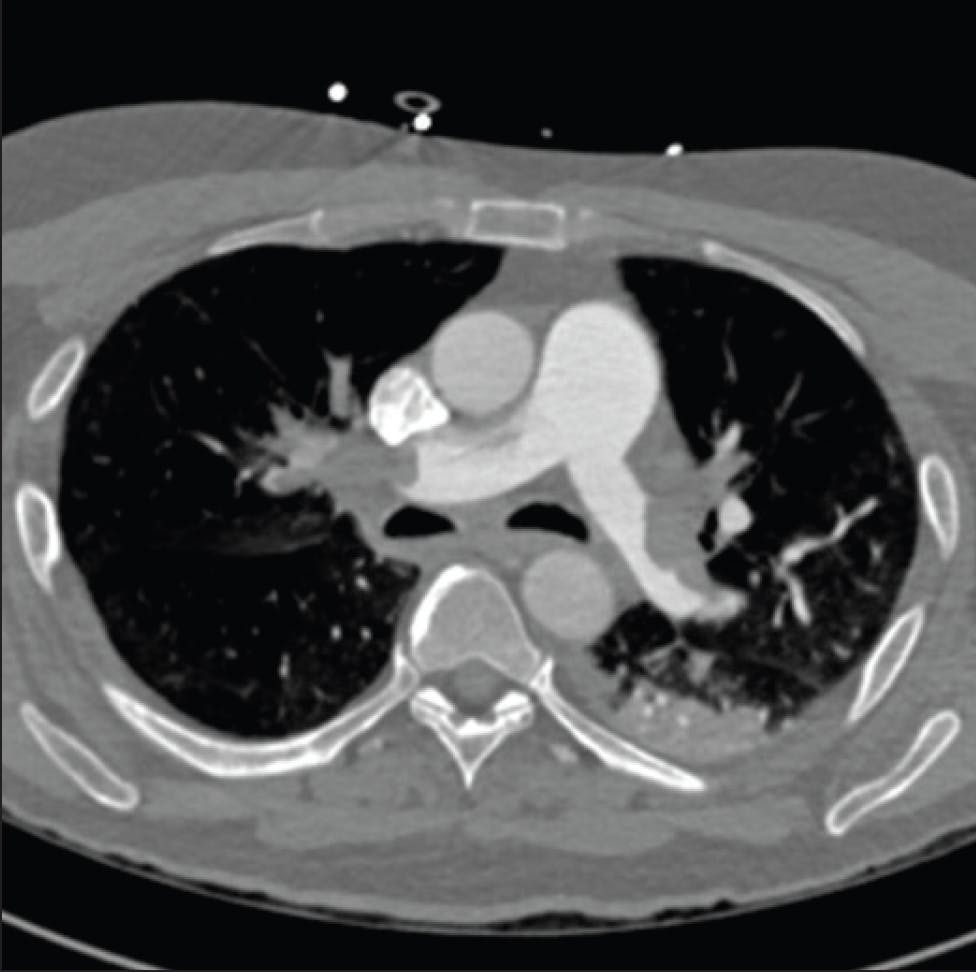

PATIENT PRESENTATION

A man in his late 60s, with history of chronic coronary syndrome, arterial hypertension, hypercholesterolaemia, type II diabetes, and chronic kidney disease, presented with progressive dyspnea and chest pain over the previous 3 days. Upon arrival, he exhibited tachycardia at 122 bpm and hypoxia, with a respiratory rate of 34 rpm, necessitating 6 L/min of supplemental oxygen via nasal cannula to maintain an oxygen saturation (SaO2) of 95%. He was normotensive (138/74 mm Hg), but had elevated troponin I as well as NT-proBNP levels and elevated lactate (2.7 mmol/L). CT pulmonary angiography revealed saddle thrombus with central bilateral clots in the both proximal pulmonary arteries (PAs) and severe RV strain with an RV/LV ratio of 1.8 (Figure 1). The diagnosis of intermediate-high–risk PE was established, and initial low-molecular wedge heparin treatment was started. Due to lack of efficacy of anticoagulative therapy and given the persistent RV failure and high proximal clot burden, the local PE Response Team qualified the patient for catheter-directed aspiration thrombectomy with the Lightning Flash 2.0 system.

Figure 1. CT pulmonary angiograms showing RV dilatation (A) and saddle PE (B).